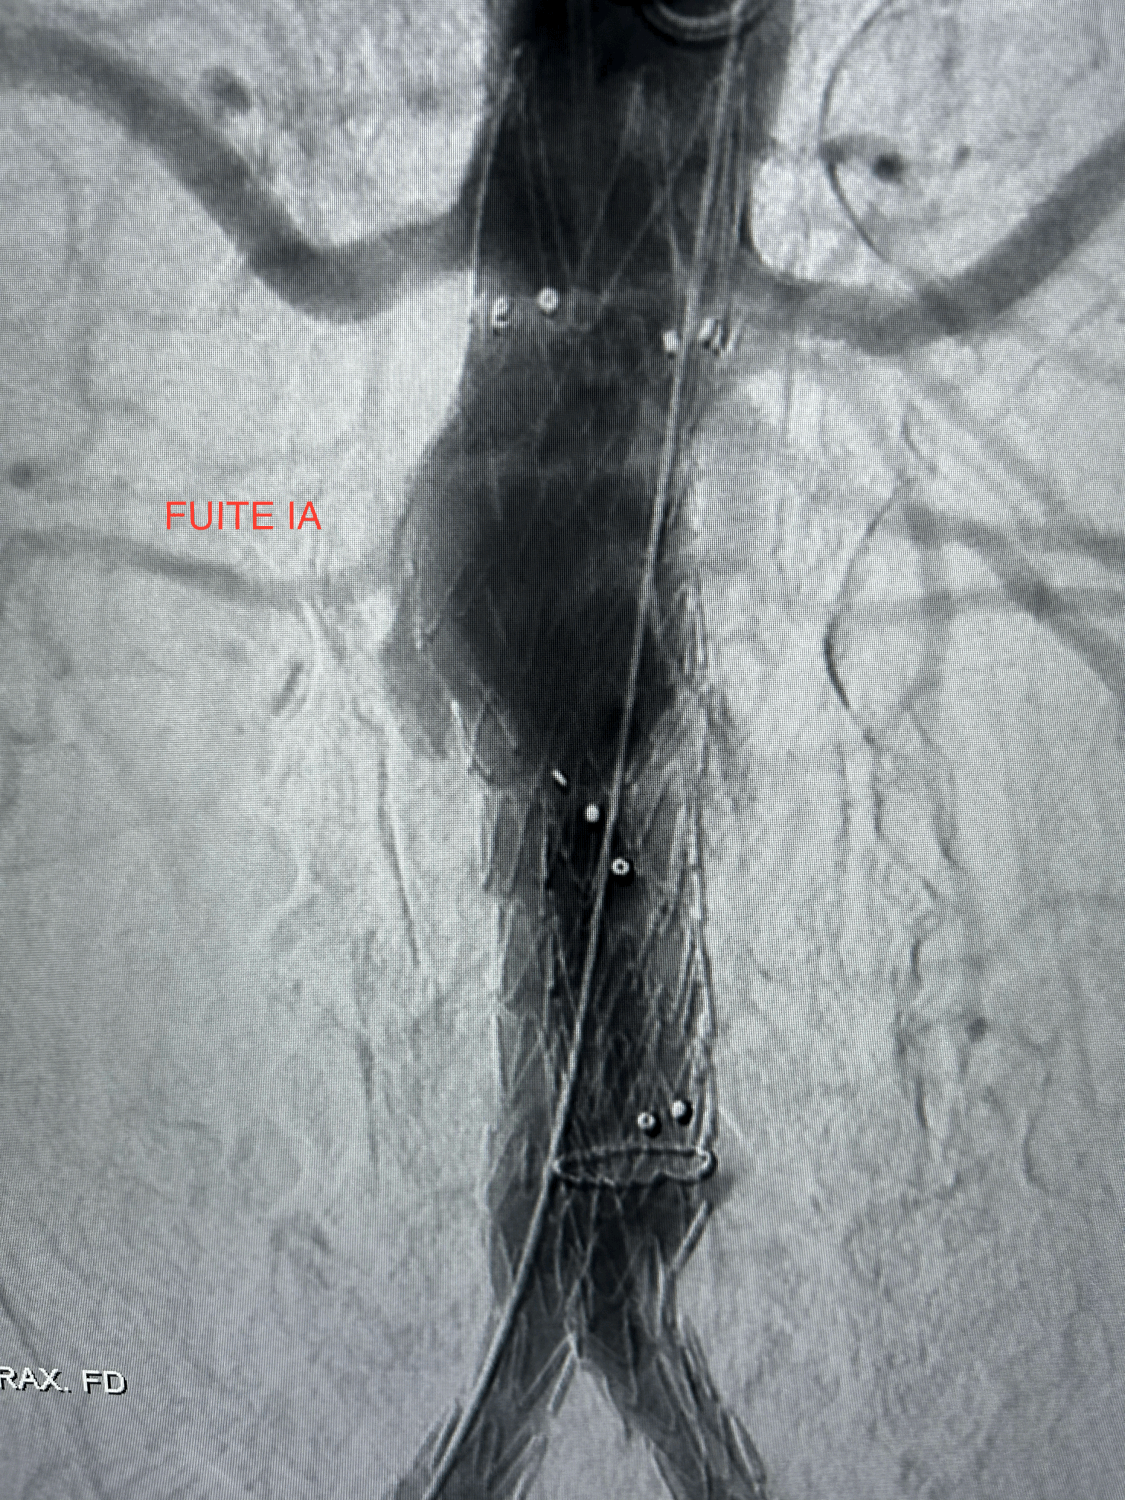

Fuite de type IA persistante au contrôle artériographique per-opératoire après inflation prolongée du collet aortique proximal et de la totalité de l'endoprothèse aortique à l'aide d'un ballon ENDURANT. Pas de possibilité de mettre en place une CUFF aortique plus proximale.

Mise en place de 8 Heli-FX EndoAnchor en "STOCK", mises en "croix", au niveau du collet aortique sous-rénal, juste en aval de l'artère rénale gauche.

Disparition immédiate et complète de la fuite de type IA sans nouvelle inflation du corps de l'endoprothèse.